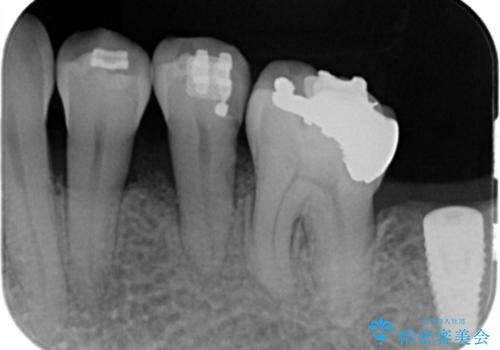

歯周病再生治療と歯周ポケット除去 歯周外科手術

- 30代女性

- 他院で歯周病を指摘され、様子見ではなく根本的な治療はないか?とご相談に来院されました。

重度の歯周病で再生療法の適応ではない最後方臼歯は抜去行い、インプラント治療、

がたつきの強い天然歯を矯正治療で整えたのち、再生治療、歯周ポケットを除去する歯周外科手術を行いました。

再生療法を行ったことで、抜歯をされてもおかしくなかった歯を、残すことができました。